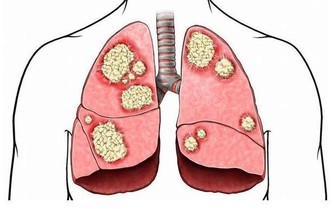

然而,屁並沒有消失,它只是隨著血液進入了全身循環,之後屁到了肝臟,會被肝臟過濾,再之後到達肺部,

最後,屁就會伴隨呼吸,被你吐出體外。經常憋屁,容易引起精神不振、消化不良、頭暈等症狀。